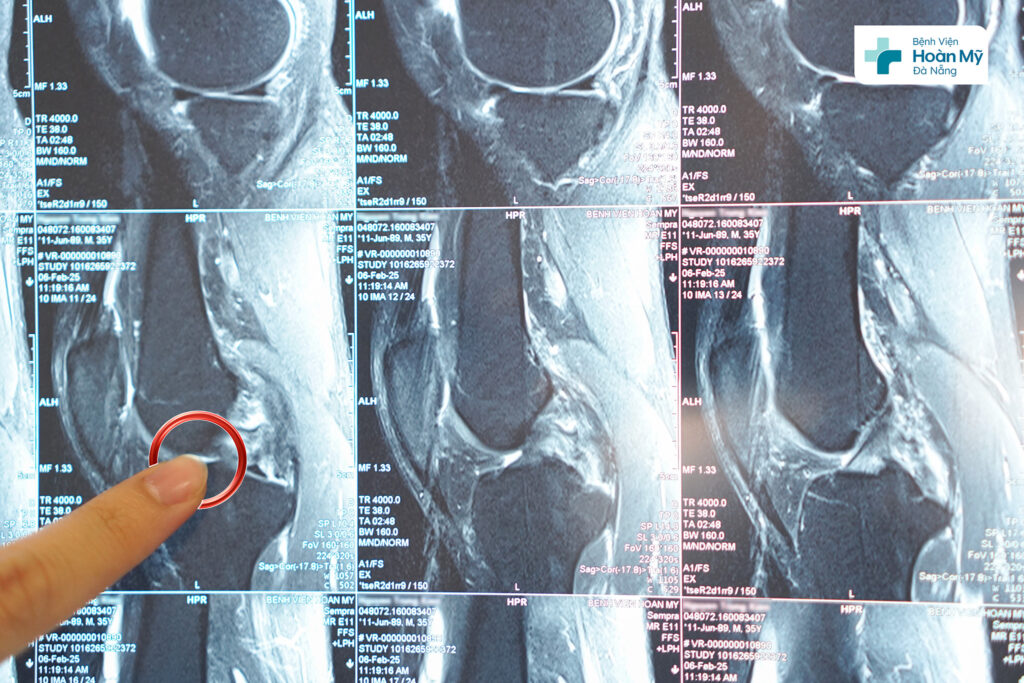

Hình ảnh dây chằng chéo sau đứt hoàn toàn trên MRI

Sau thăm khám, chụp MRI, người bệnh được chẩn đoán: đứt hoàn toàn dây chằng chéo sau gối trái. Người bệnh được thực hiện phẫu thuật nội soi tái tạo dây chằng chéo sau gối phải bằng phương pháp All INSIDE. Đây là phương pháp mới trên thế giới và được triển khai ở một số bệnh viện tuyến đầu về nội soi khớp gối ở Việt Nam. Phương pháp này cho đường mổ ít xâm lấn, thẩm mỹ, giúp người bệnh phục hồi nhanh chóng, có thể tập, vận động sớm từ đó trở lại cuộc sống bình thường sớm nhất.